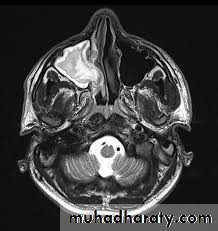

4. Magnetic resonance imaging (MRI)

MRI can be used to distinguish oxygenated blood from deoxygenated blood and named as functional magnetic resonance imaging (fMRI), and publish the first functionalimage using bold signal with T2 in 1992. The principle of RI is based

on the magnetic properties of hydrogen protons (body tissues that contain

hydrogen atoms). In MRI examination, he patient is placed in apowerful magnetic field in which the protons within the body become aligned longitudinally (TI). When increasing the radiowaves, a radiofrequency